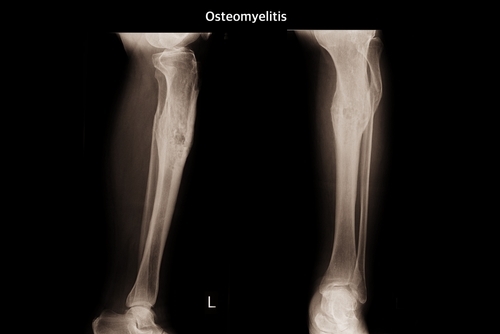

Osteomyelitis is a rare but serious condition characterised by an inflammation of bone caused by infection, generally in the legs, arms or spine. The copper implant could be surgically placed at the infection site. It would kill bacteria, improve blood flow, and promote new bone growth without using antibiotics as well as reducing the need for bone grafting.

The copper-doped bioactive glass in the porous scaffold implant attracts blood vessels and bone cells, which accelerates bone repair. The copper ions in the implant also prevent bacterial growth, said the study, published in the journal Biomaterials. People can develop osteomyelitis from broken bones, severe tooth decay and deep puncture wounds, among other causes. In the worst cases, osteomyelitis can result in amputation or be fatal.